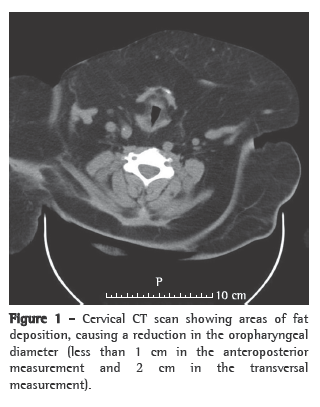

The clinical status of the patient progressively improved, with subsequent reduction in BiPAP pressures and in the use of the ventilator, which was interrupted on post-admission day 6 due to the appearance of facial ulcerations caused by the nasal mask. During the first night without noninvasive ventilation, there were long periods of oxygen desaturation (SpO2 < 88%) and snoring. The patient was then submitted to cervicofacial CT (Figures 1 and 2) and a cardiorespiratory sleep study.

The sleep study lasted approximately 8 h, revealing severe obstructive sleep apnea (apnea-hypopnea index: 37 events/h; obstructive apnea index: 29 events/h; median oxygen saturation during sleep: 88%; oxygen desaturation index: 51%/h; and minimum SpO2: 51%). The CT scan revealed various areas of fat deposition in the mediastinum, causing a reduction in the trachea caliber of 1 cm transversally and 4 cm anteroposteriorly. Continuous positive airway pressure (CPAP) titration was carried out on the second night, and the patient was discharged. At home, the patient remained on BiPAP ventilation (EPAP: 8 cmH2O; IPAP: 16 cmH2O), delivered via nasal pillows (Figure 3).